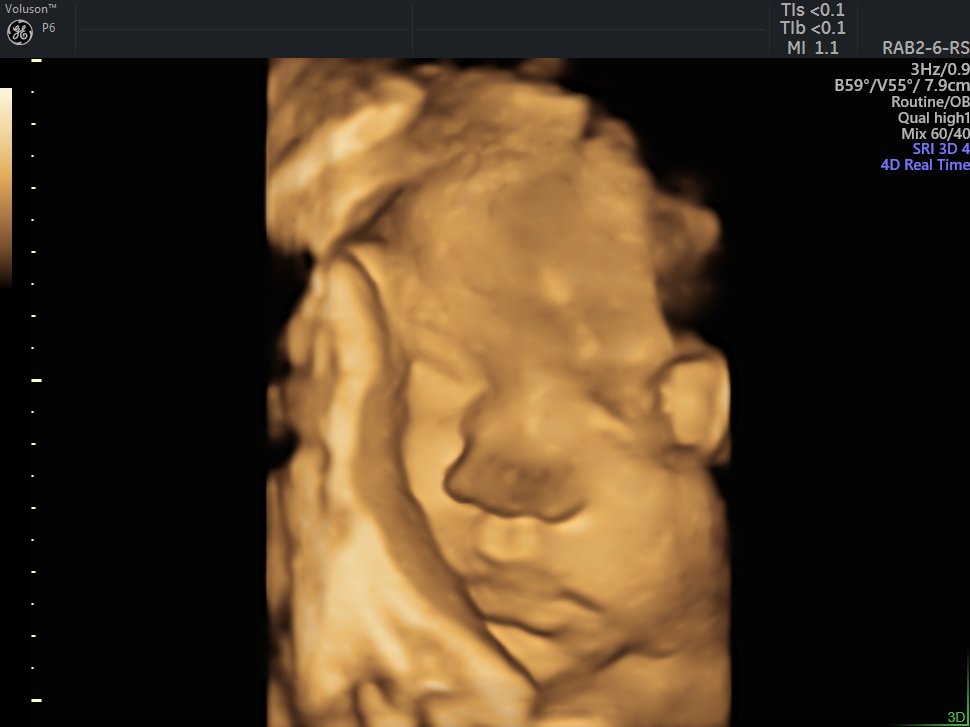

4 D Ultrasonografi

4 Boyutlu (Renkli) Ultrason ve Doppler Ultrasonografi